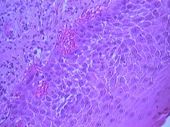

El estudio histopatológico (Nº 03-129) realizado en la Cátedra de Anatomía Patológica General y BMF de la Facultad de Odontología, informó que se trataba de una ampolla subepitelial. El epitelio se mantenía en áreas adosado a la membrana basal. El conjuntivo presentaba un infiltrado inflamatorio linfocitario, con neutrófilos, plasmocitos, abundantes mastocitos y neovasos (Fotos 8 – 10).

Foto 9 Infiltrado de linfocitos, neutrófilos y plasmocitos

Foto 10 Presencia en conjuntivo de mastocitos y neovasos. Alteración de células basales

El estudio de los tejidos en el microscopio óptico demuestra, una separación nítida entre epitelio y conjuntivo, llamada ampolla o bulla subepitelial. Este epitelio mantiene la capa de células basales y por debajo de él, se observan desde suaves hendiduras a francas luces subepiteliales que se extienden a lo largo de la superficie.

El techo que conforma la parte superior de la ampolla está constituido por un epitelio atrófico y comprimido en todo su espesor. El contenido de estas ampollas es sero-fibrinógeno con eosinófilos y neutrófilos. El inicio de la enfermedad se caracteriza por una reacción inflamatoria rica en eosinófilos y linfocitos, pero con escasos plasmocitos, dispuestos en forma difusa hacia la profundidad del tejido conectivo papilar edematoso.

En general el infiltrado inflamatorio es de grado variable en el tejido conjuntivo, con abundantes células plasmáticas y a veces con presencia de eosinófilos y neutrófilos. Además existe dilatación de los vasos sanguíneos, acompañado por un moderado infiltrado inflamatorio que abarca de la superficie hasta la profundidad del corion.

La repetición de los brotes evolutivos en la misma zona, conduce a la atrofia de las papilas del corion y a la neoformación de los vasos capilares, con reacción fibrosa y acúmulos de densos infiltrados linfoplasmocitarios.